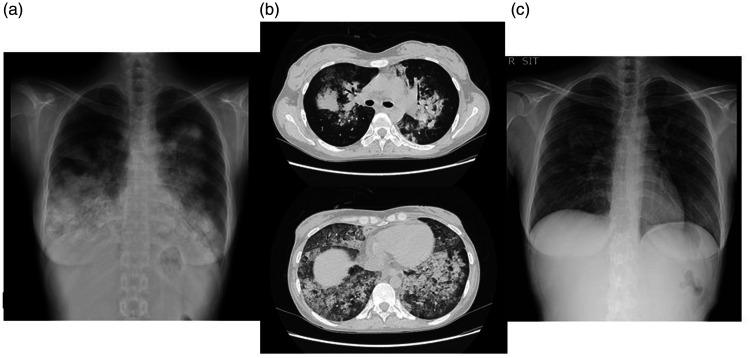

A 29-year-old woman with chronic, prolonged pustular psoriasis was admitted to our hospital because of high-grade fever and a systemic skin rash. General examination revealed a whole-body skin rash and superficial lymphadenopathy. Peripheral blood examination showed unclassified cells positive for CD3, CD4, and T-cell receptor αβ, and negative for CD20 and CD56. Soon after administration, she developed acute respiratory failure and required artificial ventilation. Bronchoalveolar lavage fluid showed increased numbers of eosinophils and abnormal lymphocytes of the same phenotype in peripheral blood and skin. She was diagnosed with eosinophilic pneumonia, and her respiratory failure was improved by corticosteroid therapy. Based on the histological findings of skin, lymph node, and bone marrow biopsies, a diagnosis of peripheral T-cell lymphoma not otherwise specified (PTCL-NOS), with positivity for CC chemokine receptor 4 was made. She received chemotherapy followed by allogeneic stem cell transplantation, which resulted in complete remission of her PTCL-NOS. She remained alive and disease-free 6 years later. This is the first reported case of PTCL-NOS developing during the clinical course of pustular psoriasis. The clinical manifestations of PTCL-NOS are complex, but an accurate diagnosis and appropriate therapy may produce a good clinical outcome in patients with PTCL-NOS.

一位 29 岁的女性患有慢性、迁延性脓疱性银屑病,因高热和全身性皮疹入住我院。全身检查发现全身皮疹和浅表淋巴结病。外周血检查显示未分类细胞 CD3、CD4 和 T 细胞受体 αβ 阳性,CD20 和 CD56 阴性。用药后不久,她出现急性呼吸衰竭,需要人工通气。支气管肺泡灌洗液显示外周血和皮肤中嗜酸性粒细胞和异常淋巴细胞数量增加,表型相同。她被诊断为嗜酸性粒细胞性肺炎,皮质类固醇治疗改善了她的呼吸衰竭。根据皮肤、淋巴结和骨髓活检的组织学发现,诊断为未分类的外周 T 细胞淋巴瘤(PTCL-NOS),CC 趋化因子受体 4 阳性。她接受了化疗和异基因造血干细胞移植,PTCL-NOS 完全缓解。6 年后,她仍然存活且无疾病。这是首例脓疱性银屑病病程中发生 PTCL-NOS 的报道。PTCL-NOS 的临床表现复杂,但准确的诊断和适当的治疗可能会给 PTCL-NOS 患者带来良好的临床结局。